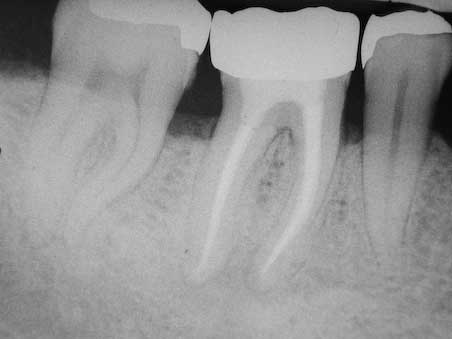

WF -Kontrolle 6 Monate post WF

Veröffentlicht 16. Februar 2009 am 452 × 339 in Apikale Aufhellung (3)